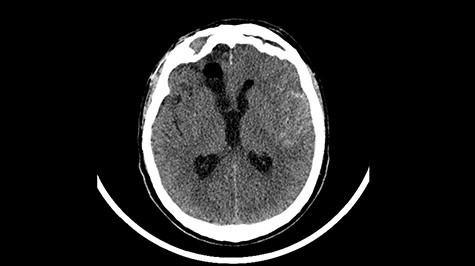

A 49-year-old patient presented after surgical treatment of nasal polyps, with headache and consciousness disorders (behavioral changes, drowsiness and allophenic orientation disorders). Computed tomography (CT) scan showed (Fig. 1) a presence of blood in fluid spaces, widening of the ventricular system (without active hydrocephalus features) and presence of air in the frontal horns of the lateral ventricles and features of cerebral edema. Due to the subarachnoid hemorrhage, an angio-CT and CT scan was performed, showing no vascular malformation. The patient's condition deteriorated with a drop in Glasgow Coma Scale (GCS) to 9, strongly expressed meningeal syndrome and a fever of > 38°C. In the performed cerebrospinal fluid examination a typical picture for bacterial infection, cultures negative. Treatment was implemented in accordance with the neuro-infections algorithm. Clinical and laboratory features of neuroinfections have withdrawn. The neurological condition of the patient improved to GCS 11. Control head CT (Fig. 2) showed enlargement of the ventricular system with cerebrospinal fluid transudation.

Head CT—state before VP shunt implantation. (Department of Neurosurgery own material).

After improvement of patient’s neurological status, a CT scan of the head revealed enlargement of the ventricular system with the features of cerebrospinal fluid transudation (Fig. 2), thus the patient has been qualified for a VP shunt implantation (Fig. 6).